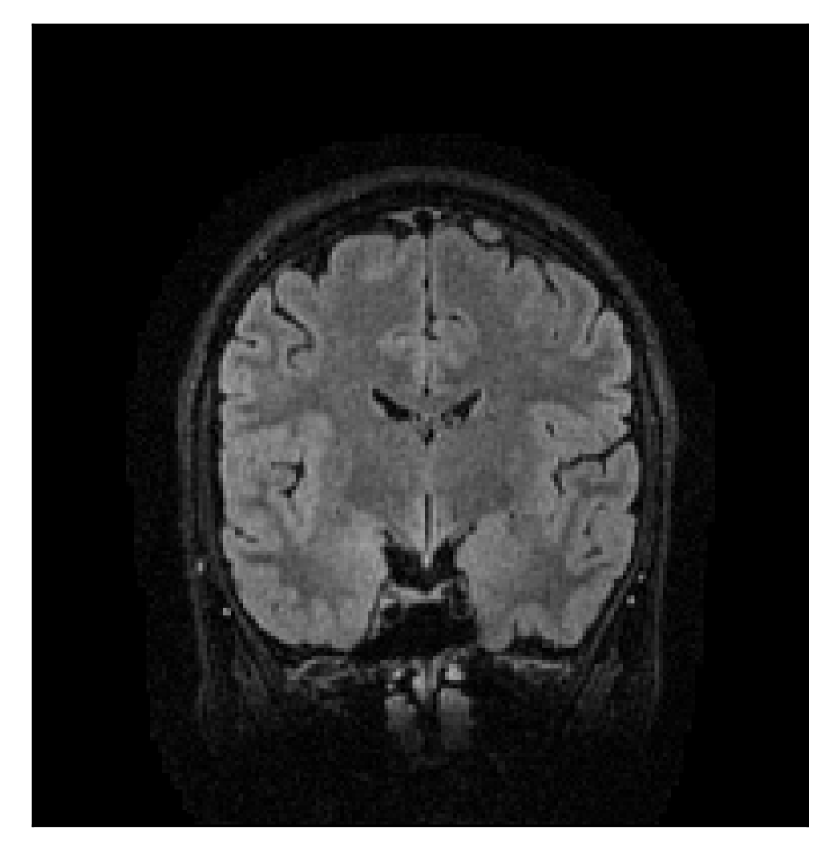

3.2 Experiment 2: on the choice of the reference contrast

This in-vivo experiment tests the proposed correction scheme with respect to a different combination of corrupted and reference contrast, namely a T1-weighted corrupted contrast with a T2-weighted reference contrast (see Table 1). For this experiment, we prompt volunteer 2 to move five times during the acquisition. The corrupted acquisition employs randomized sampling.

In Section 4.2, we gather the results for this experiment.

| Section 3.2, Figure 10 | Sagittal | 25.84 | 28.07 | 0.7032 | 0.8093 |

| Coronal | 26.35 | 30.40 | 0.7851 | 0.9021 | |

| Axial | 28.11 | 30.54 | 0.8248 | 0.9012 | |

The motion-corrected full-volume scans were analyzed by a neuroradiologist with 16 years of experience. These were generally deemed of good radiological quality. The motion-related artifacts have been completely removed, and the results are quite close to the ground truth. In Table 3, we organized a more detailed qualitative analysis of the 3D results, geared toward a radiological assessment of the corrected scans.

| Experiment | Contrast | Motion resolution | Blurring | Artifacts | Additional comments |

| Section 3.2, Figure 10 | T1 | Completely corrected | Some blurring | No additional artifacts | Good grey white matter differentiation, |

| some loss of grey matter low signal | |||||

4.2 Experiment 2: choice of the reference contrast

With the experiment described in Section 3.2, we demonstrate the flexibility of the correction scheme with respect to the choice of the reference contrast. The results are shown in Figure 10. Contrary to the experiments detailed in the previous section, we are now considering a T2-weighted reference contrast to guide the correction of a T1-weighted corrupted contrast. The quality of the correction indicates that the proposed technique is rather flexible in terms of reference contrast.

Furthermore, the flexibility of the proposed motion-correction method is demonstrated with different combinations of motion-corrupted and reference contrasts (Section 4.2). Our experience suggests that an important factor in assessing the effectiveness of the reference contrast as a guide for motion correction lies in the similarity of the -space distribution of the two contrasts. Good reconstruction quality can be expected when the reference contrast has similar or higher frequency content when compared to the corrupted contrast, regardless of the type of contrast considered.

Sagittal

Coronal

Axial

Coronal detail